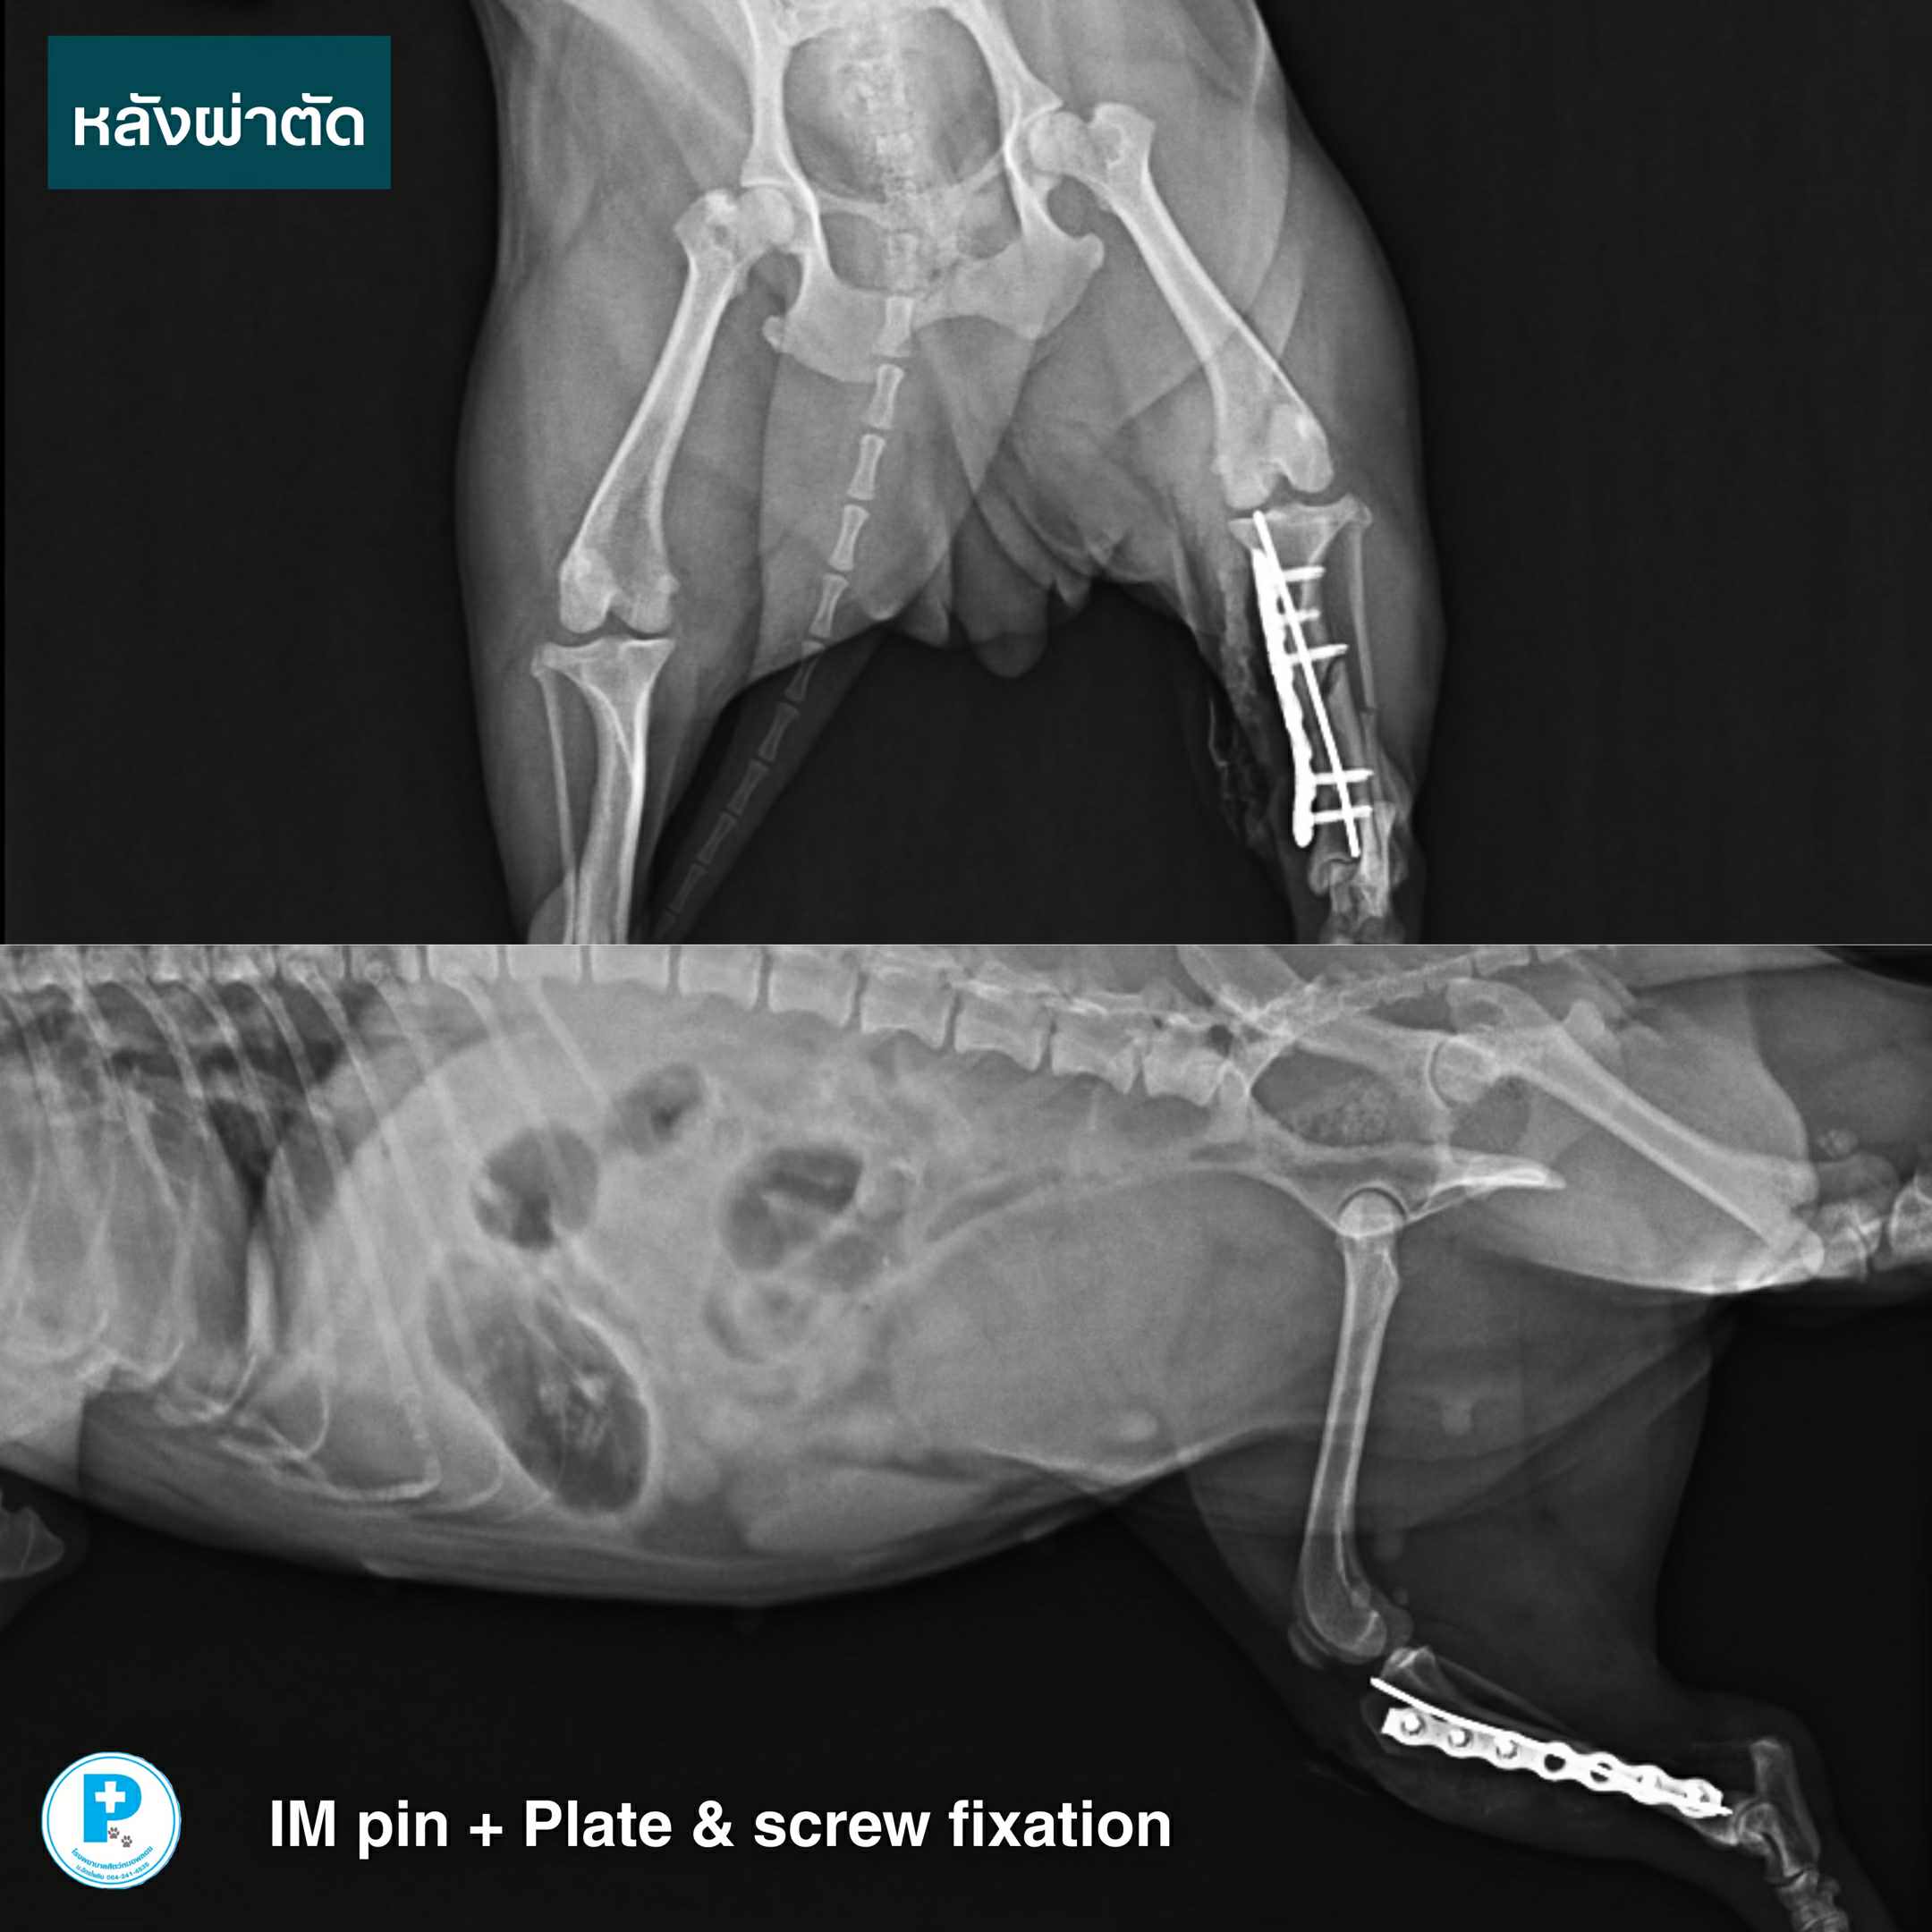

ทีมสัตวแพทย์จึงเลือกการรักษาด้วย IM pin ร่วมกับ Plate & screw fixation เพื่อเพิ่มความแข็งแรง ควบคุมแรงบิด และช่วยให้กระดูกเชื่อมติดได้อย่างปลอดภัย

หลังผ่าตัด น้องมีตังค์อยู่ในช่วงพักฟื้นติดตามอาการอย่างใกล้ชิด

กระดูกหักมีหลายตำแหน่งและหลายรูปแบบ การเลือกวิธีผ่าตัดที่เหมาะสมตั้งแต่ครั้งแรก ช่วยลดโอกาสการผ่าซ้ำ และทำให้น้องกลับมาเดินได้เร็วที่สุด